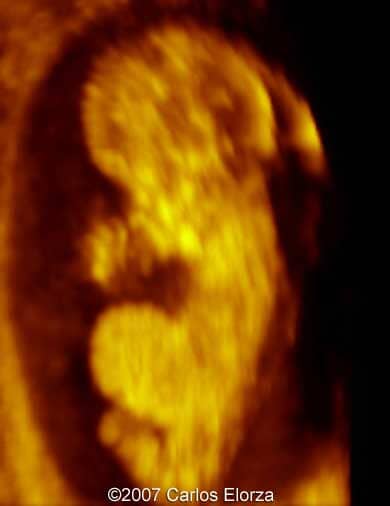

Trisomy 13

Carlos A. Elorza, MD.

Chief of Ultrasonography Department, Hospital Italiano Garibaldi, Rosario, Argentina.

38-year-old woman (G3, P2)Ā presented in our department at 10th week of pregnancy. Ultrasound examination discovered striking nuchal edema and omphalocele with liver"s exenteration. A chorionic biopsy revealed trisomy 13. Here are someĀ images that we obtained.